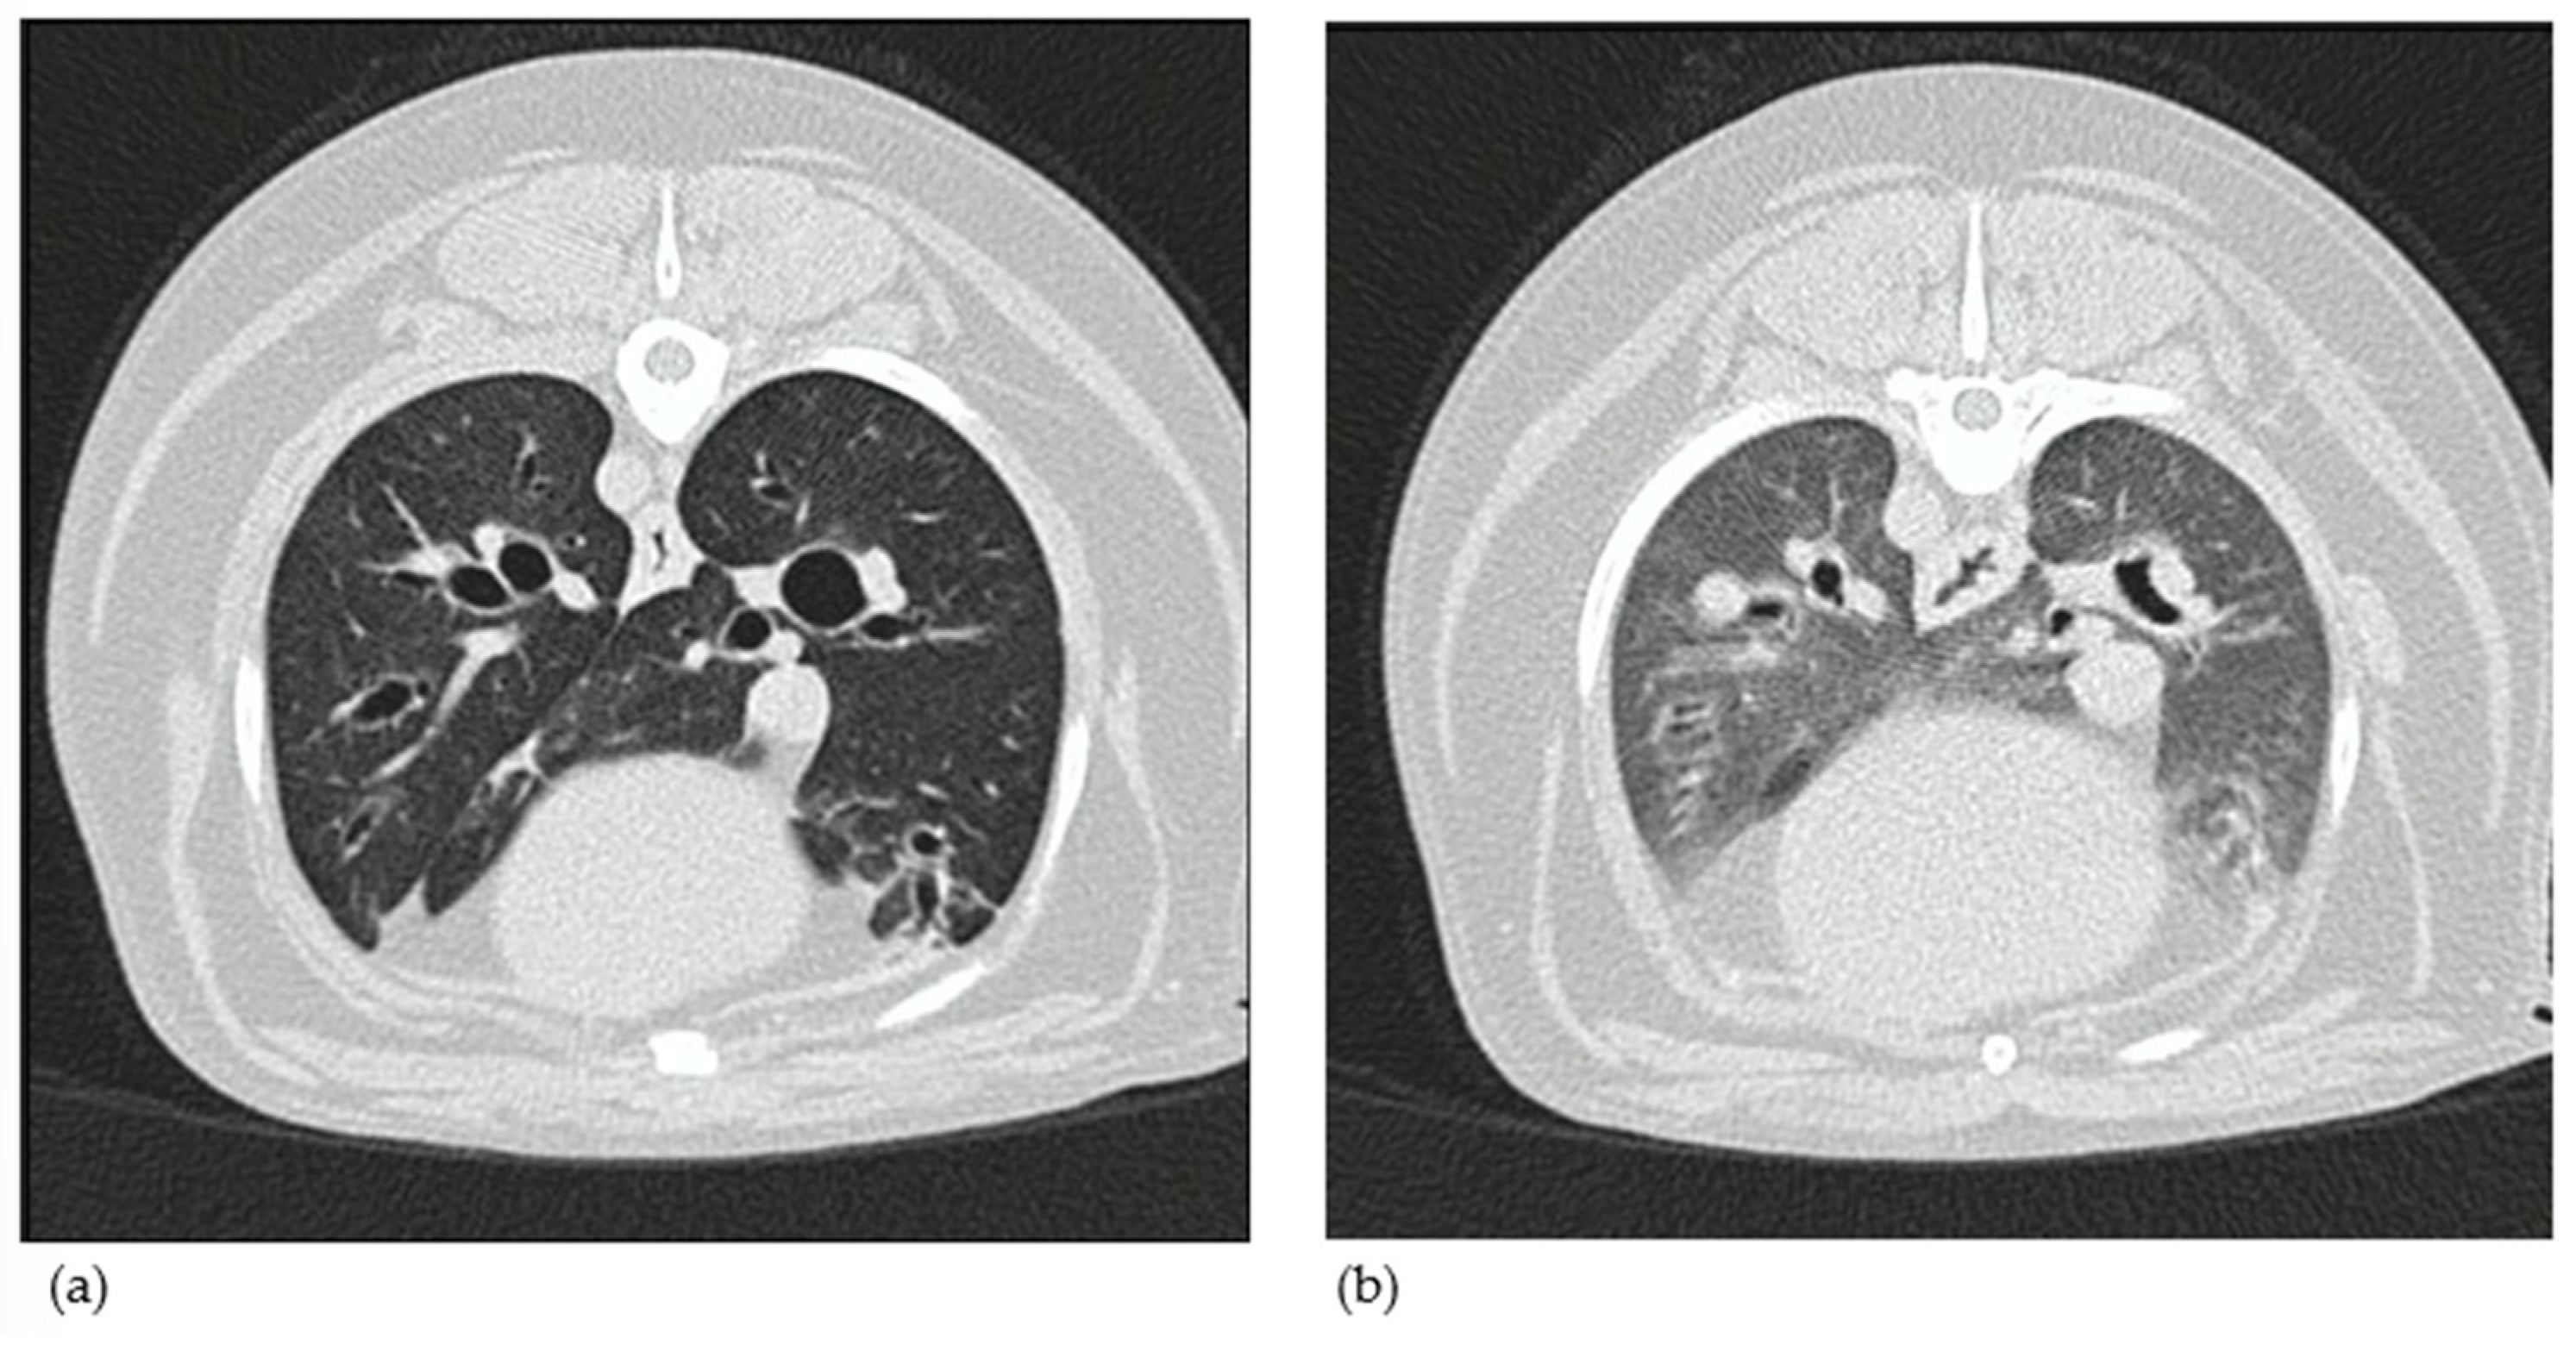

3.1.8. Computed Tomography Findings

3.2.2. Thoracic CT Versus Endoscopy